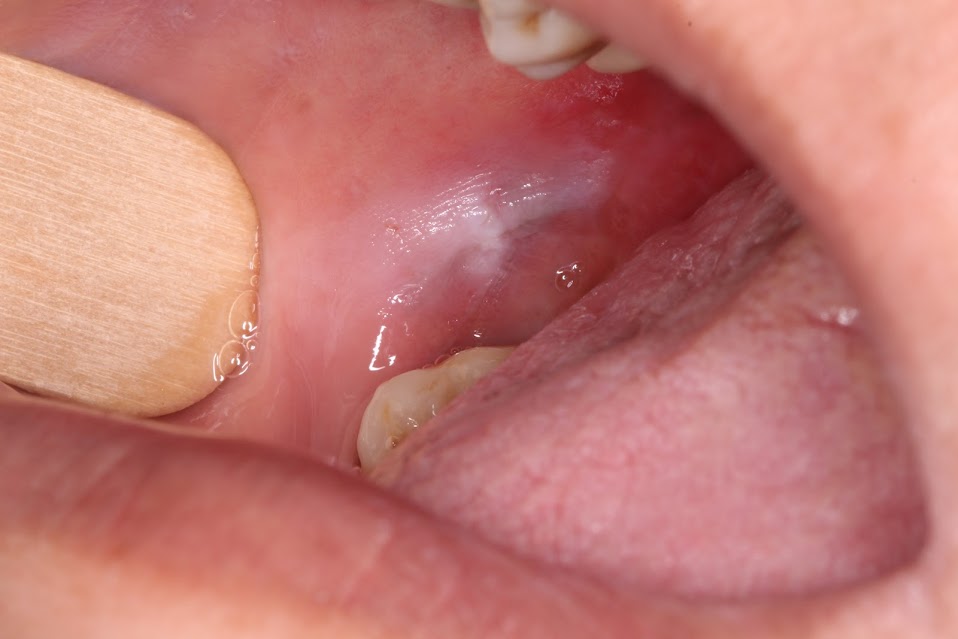

This month’s case features a bump on the gum. The main differential diagnosis for these lesions include pyogenic granuloma, peripheral giant cell granuloma, and peripheral ossifying fibroma.

The main entities in the differential diagnosis are all reactive lesions rather than true neoplasms. They represent a growth on the gingiva occurring in response to something such as calculus build up. In pathology, the word ‘peripheral’ means ‘on the gingivae’ – therefore, the only place one can encounter a peripheral ossifying fibroma or peripheral giant cell granuloma is the gingiva. Though 75% of pyogenic granulomas occur on the gingivae, they can also occur anywhere in the oral cavity. Pyogenic granulomas are also known as “pregnancy tumors” as they occur with higher frequency in pregnant women, though men and non-pregnant women can also get pyogenic granulomas.

The best treatment for these lesions is surgical excision with submission for histologic evaluation. This is the treatment for a couple of reasons – first, the lesions will not go away without a biopsy. Second, we do need to rule out the rare cases of malignancy presenting as reactive bumps on the gum. Inform the patient that all three have about a 10-15% recurrence rate.